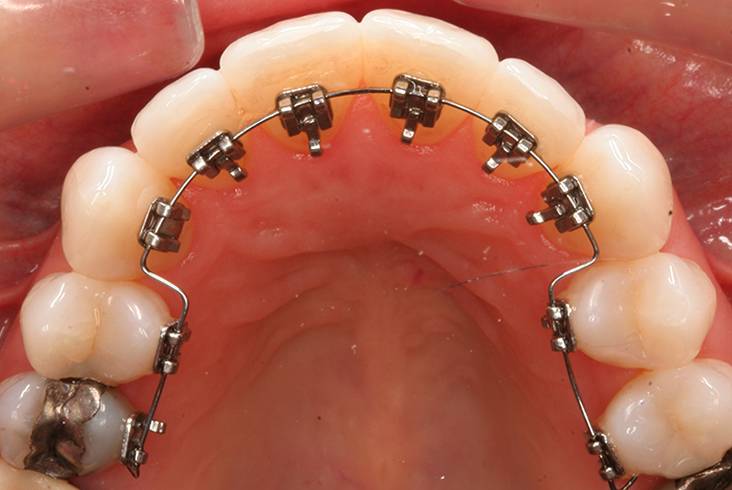

Главное достоинство лингвальных скоб в их незаметности. Их выбирают люди, которым приходится постоянно вести переговоры, выступать перед публикой и пр. Также их часто ставят детям. Минусы таких систем следующие:

Лингвальные, или внутренние системы крепятся на внутренней стороне зубов. Их не видно со стороны, поэтому такие брекеты подойдут подростку, который стесняется носить на зубах какие-то конструкции

Родителям важно знать, что внутренние брекеты стоят дороже внешних. В некоторых случаях могут появиться небольшие проблемы с дикцией, которые обычно быстро проходят по мере привыкания

Виды брекетов

Кроме того, можно сделать незаметными и металлические беркеты. Для этого брекеты крепят на заднюю, язычную (лингвальную) поверхность зубов. Такие брекеты называют лингвальными. Они абсолютно незаметны, но эффективны только против некоторых аномалий прикуса. Особенно хорошо они справляются с выдвижением зубного ряда чуть вперед, так как давят на него изнутри. Такие брекеты стоят от 100 тысяч рублей.

- Лингвальные брекеты тоже подходят для пациентов разного возраста, в том числе детей. Но для установки нужна достаточная длина зубов. Внутренние брекеты стоят дорого, не подходят для коррекции сложных аномалий прикуса. Основной плюс — не так заметны на зубах.

- Лингвальные брекеты могут быть изготовлены из любых перечисленных материалов. Так называется система, которая крепится с внутренней стороны зубов и невидима глазу окружающих. Такие брекеты часто применяют при установке на передние резцы с сохранением эстетики зубного ряда.